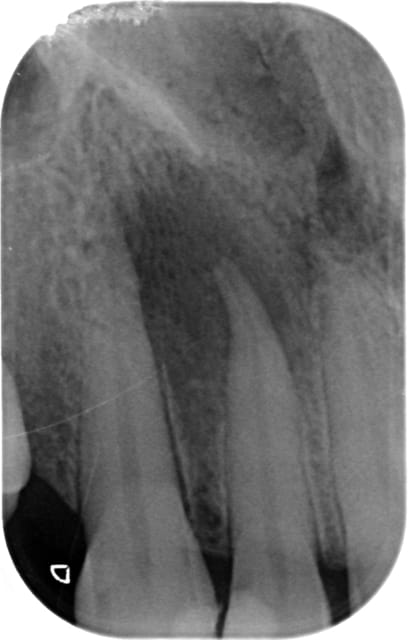

Thermafil / Puff post abcès apical aigu

J'ai très souvent ce type de résultat avec le Thermafil sur des dents présentant un abcès apical aigu.

Quand tu vois la taille de l apex initial, tu as des chances d 'avoir un joli puff, je passe des limes de conicité supérieure à LOT-2 avant, et très peu de ciment à l apex, et ça marche pas toujours :) ( J ai pas de thermafil )

Dans ce type de cas, je mets du ciment seulement sur les 2/3 de la LT car je préfère eviter les puffs.